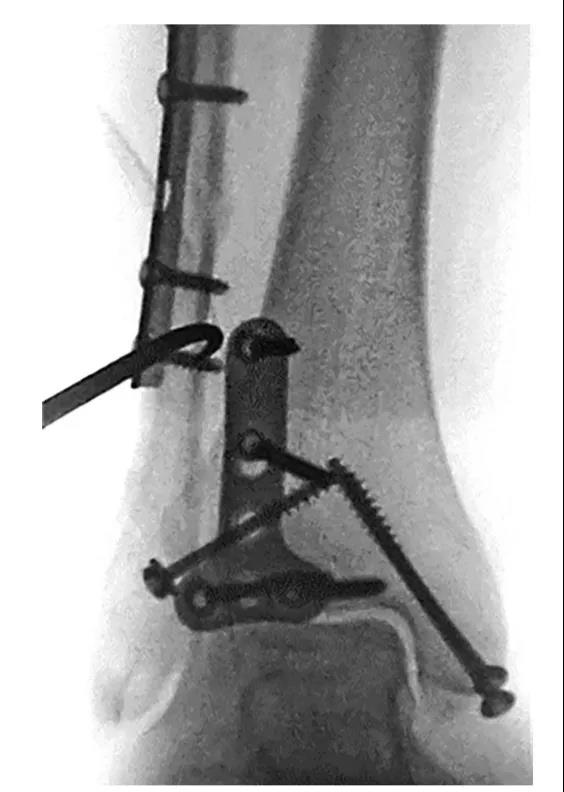

③ 首先俯卧位后外侧入路固定后踝,存在夹层骨块可行克氏针临时固定后抗滑钢板固定后踝。

④ 固定后踝后,经同一后外侧切口固定外踝,通常建议采用后侧钢板固定,如腓骨骨折线过高,则重新切口外侧钢板固定腓骨。⑤ 内踝常规切口固定内踝。⑥ 俯卧位患者屈曲膝关节,经前外侧切口固定前踝骨折块,通常选用2.7mm或3.5mm螺钉,并使用垫圈。

⑧ 复位后典型病例图。